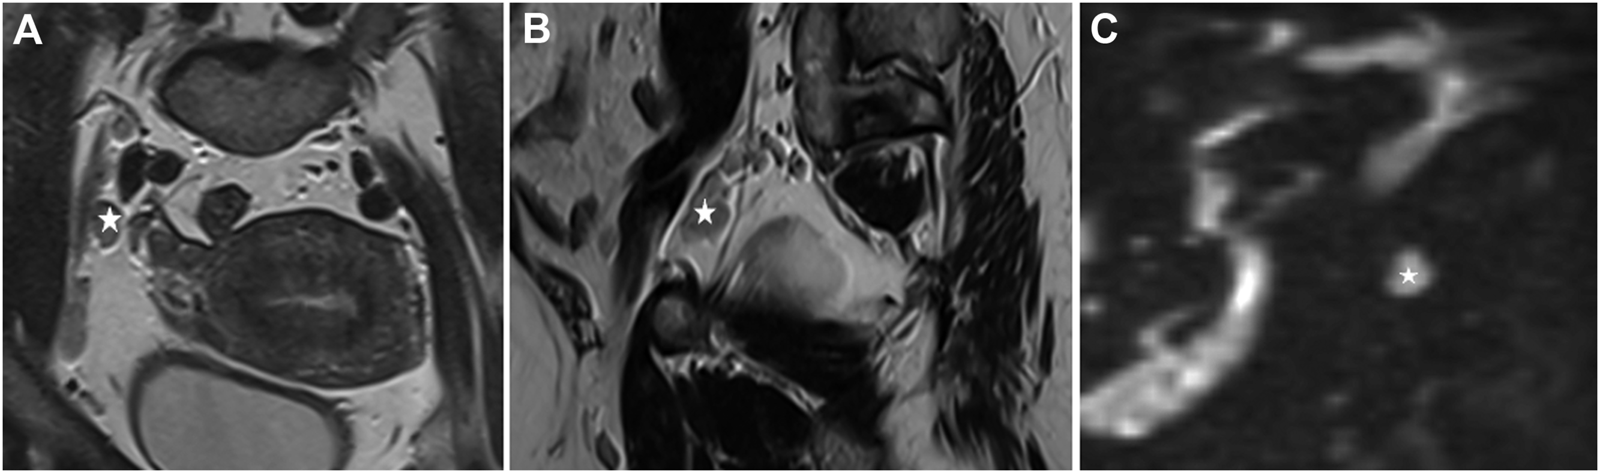

FIGURE 2

Endometrial cancer, stage T1b. *: Enlarged lymph nodes (A). T2 sequence, coronal view, enlarged lymph nodes near the external iliac artery, (B) T2 sequence, sagittal view, an enlarged lymph node near the external iliac artery, (C) enlarged lymph node, postcontrast DWI (Diffusion-weighted magnetic resonance imaging, b:800).